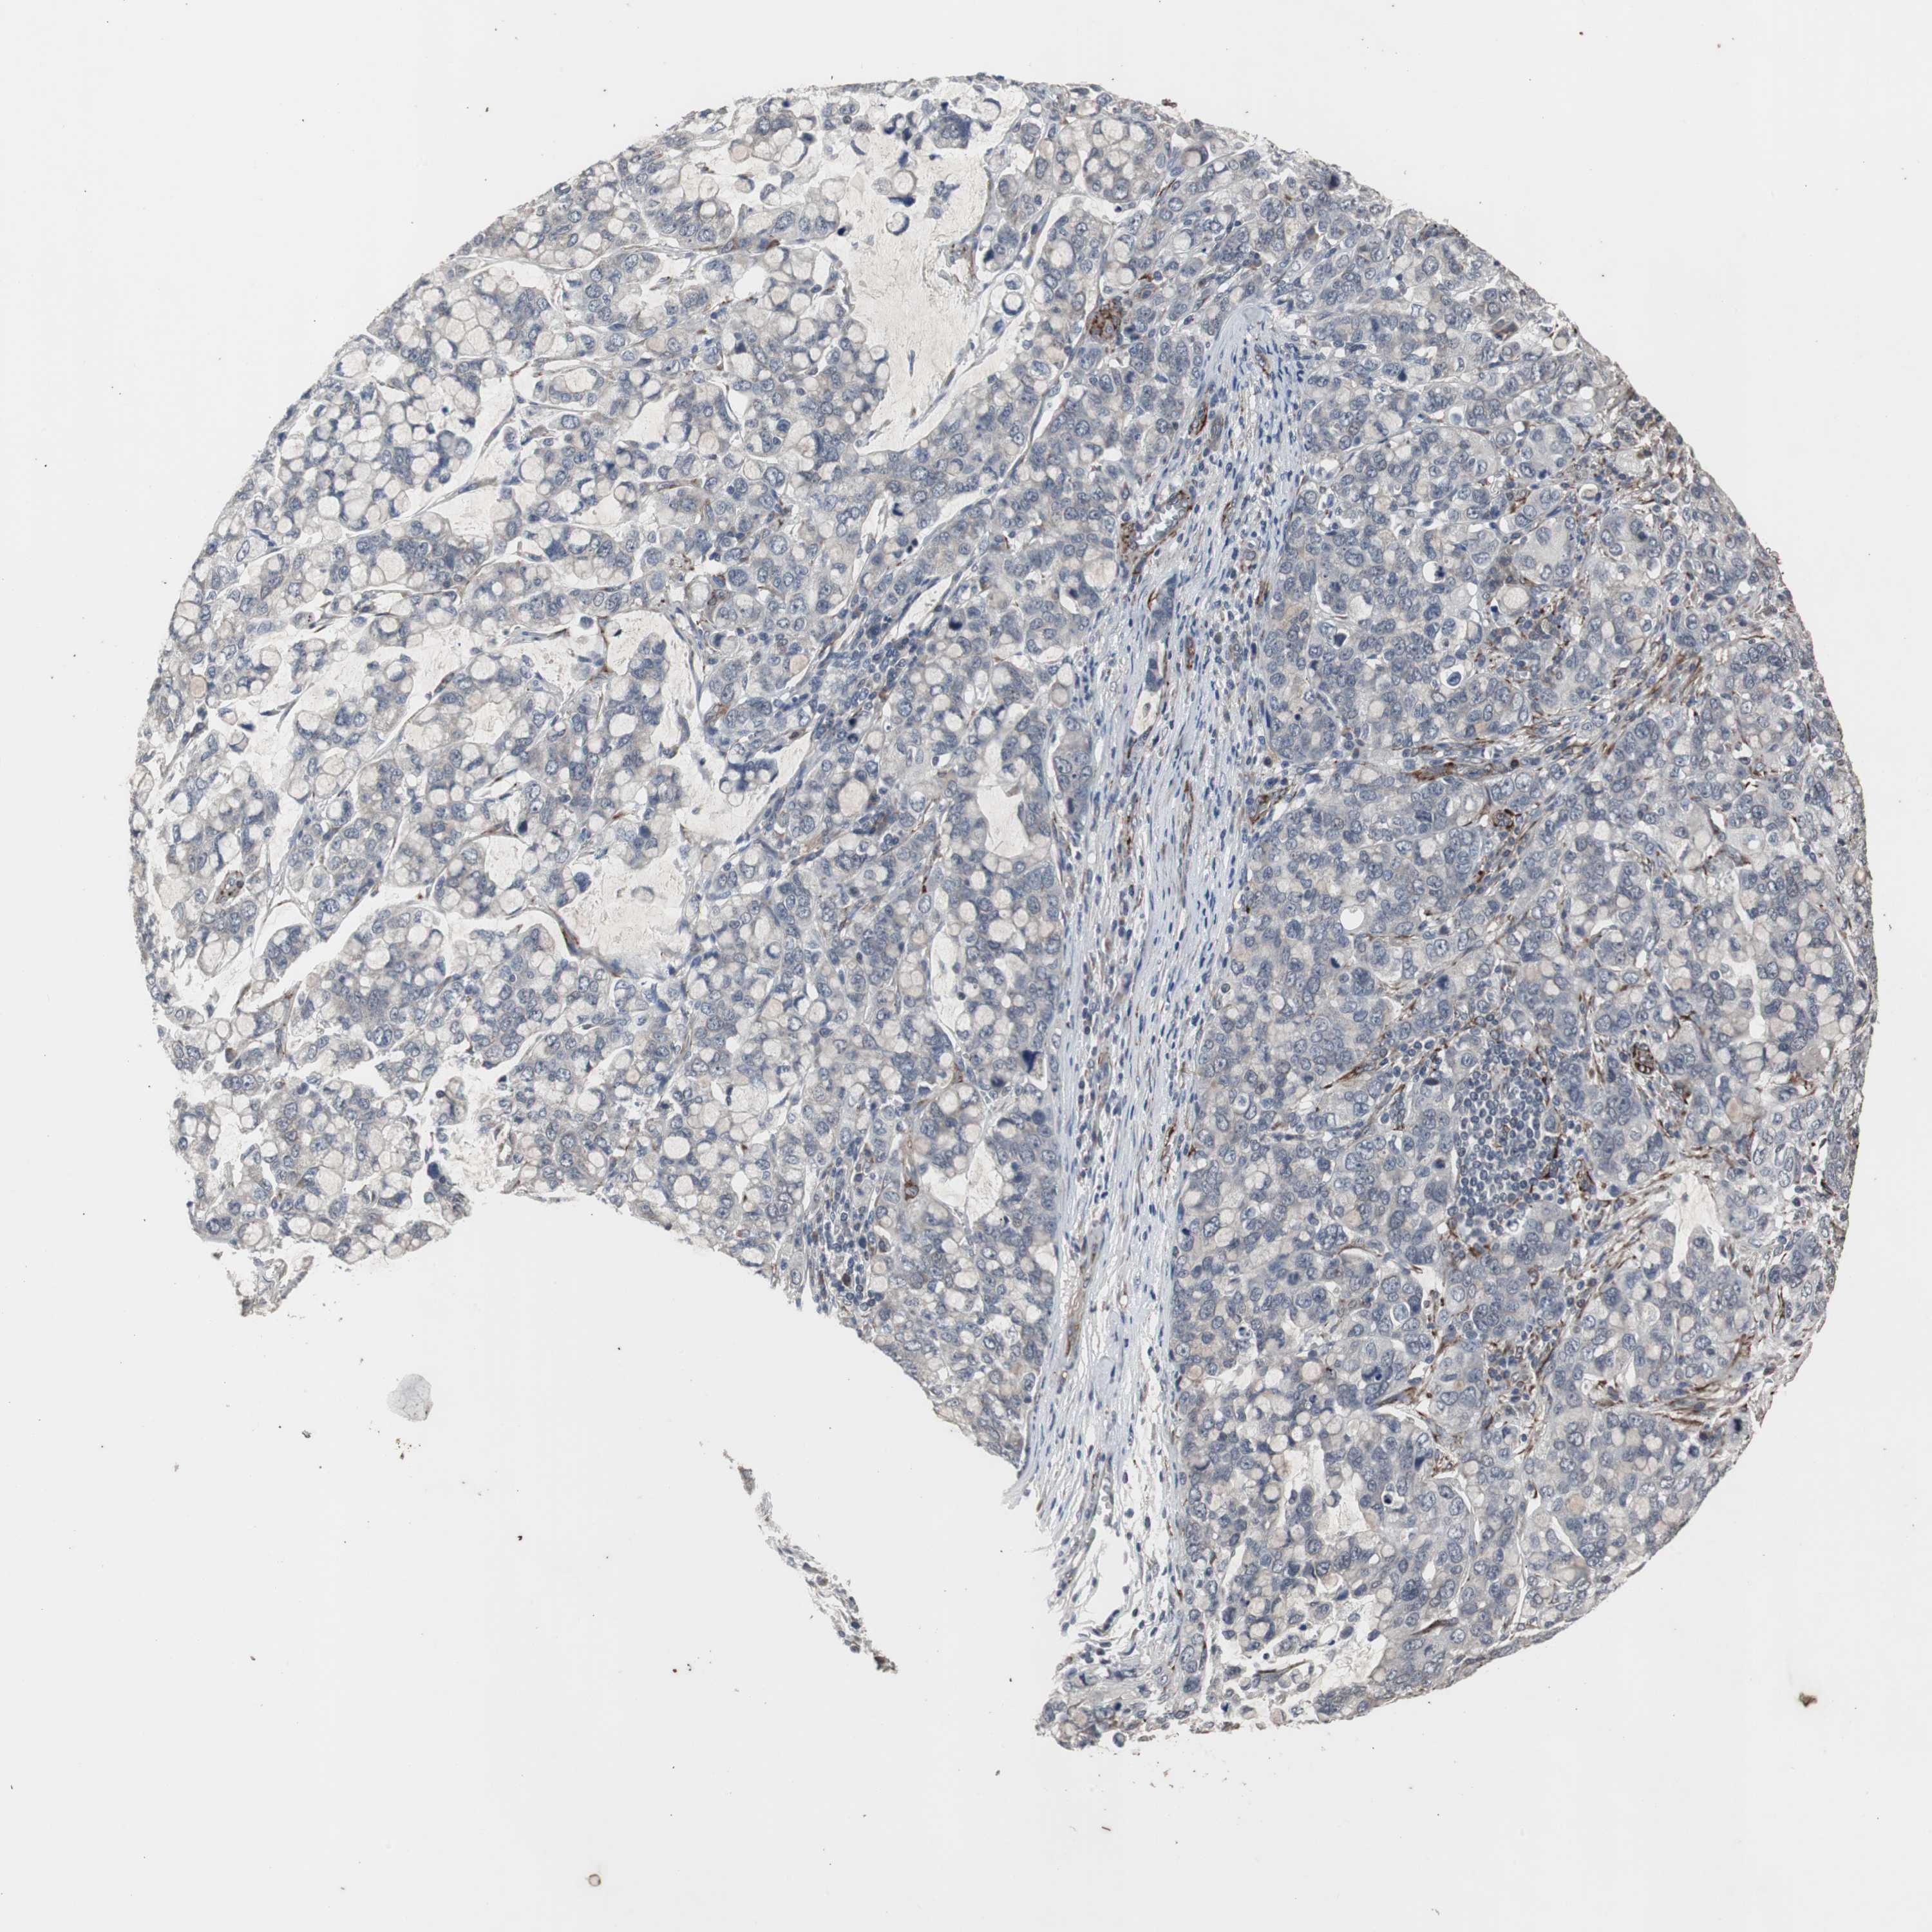

STOMACH CANCER - Protein expressioni

A mouse-over function shows sample information and annotation data. Click on an image to view it in a full screen mode. Samples can be filtered based on level of antibody staining by selecting one or several of the following categories: high, medium, low and not detected. The assay and annotation is described here.

Note that samples used for immunohistochemistry by the Human Protein Atlas do not correspond to samples in the TCGA dataset.

Antibody stainingi

Antibody staining in the annotated cell types in the current human tissue is reported as not detected, low, medium, or high, based on conventional immunohistochemistry profiling in selected tissues. This score is based on the combination of the staining intensity and fraction of stained cells.

Each image is clickable and will lead to virtual microscopy that enables deeper exploration of all samples and also displays staining intensity scores, fraction scores and subcellular localization as well as patient and tissue information for each sample.

Antibody CAB005337

Staining

High

Medium

Low

Not detected

Intensity

Strong

Moderate

Weak

Negative

Quantity

>75%

75%-25%

<25%

None

Location

Nuclear

Cytoplasmic/membranous

Cytoplasmic/membranous,nuclear

Adenocarcinoma, NOS

Adenocarcinoma, High grade